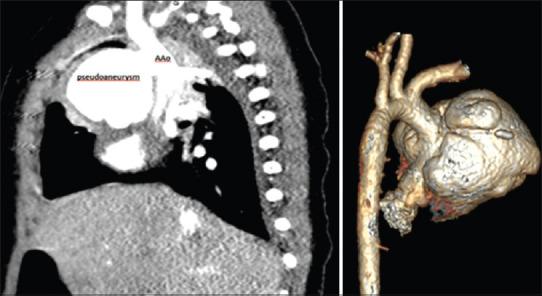

Mycotic pseudoaneurysm of the aorta is a rare and lethal complication of pediatric congenital heart surgery. We report the lethal consequences of recurrent mycotic pseudoaneurysm in an 18-month-old baby, early after subaortic membrane resection. We managed to repair the pseudoaneurysm successfully by replacing the infected ascending aorta using bovine jugular vein graft, but unfortunately, the patient developed new pseudoaneurysm at the site of anastomosis which led to his death. Although prompt diagnosis and surgical management can save the patient life, uncontrolled infection can lead to the recurrence of the problem and lethal results.

主动脉霉菌性假性动脉瘤是小儿先天性心脏手术罕见且致命的并发症。我们报告了一名18个月大婴儿在主动脉下膜切除术后早期复发性霉菌性假性动脉瘤的致命后果。我们通过使用牛颈静脉移植物替换感染的升主动脉成功修复了假性动脉瘤,但不幸的是,患者在吻合部位出现了新的假性动脉瘤,最终导致死亡。尽管及时诊断和手术治疗可以挽救患者生命,但感染控制不佳会导致问题复发并产生致命后果。